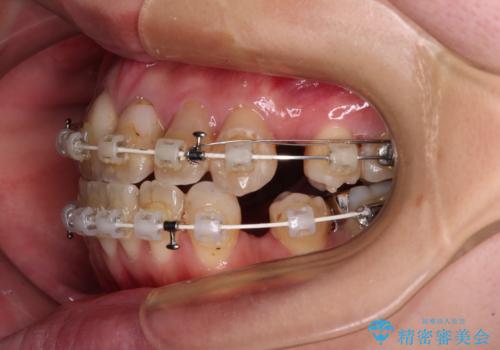

- 矯正装置

- 審美装置

口元の突出感はありませんが、前歯の重なりが著しいため、目立ちにくい表側のワイヤー装置にて、上下左右の第一小臼歯4本を抜歯して矯正治療を行うこととしました。

4本とも歯根部先端の骨が炎症により吸収していることがレントゲン写真から示唆されたため、矯正治療後に4本を再根管治療し、その後上顎6歯をオールセラミッククラウンにて補綴治療することとしました。